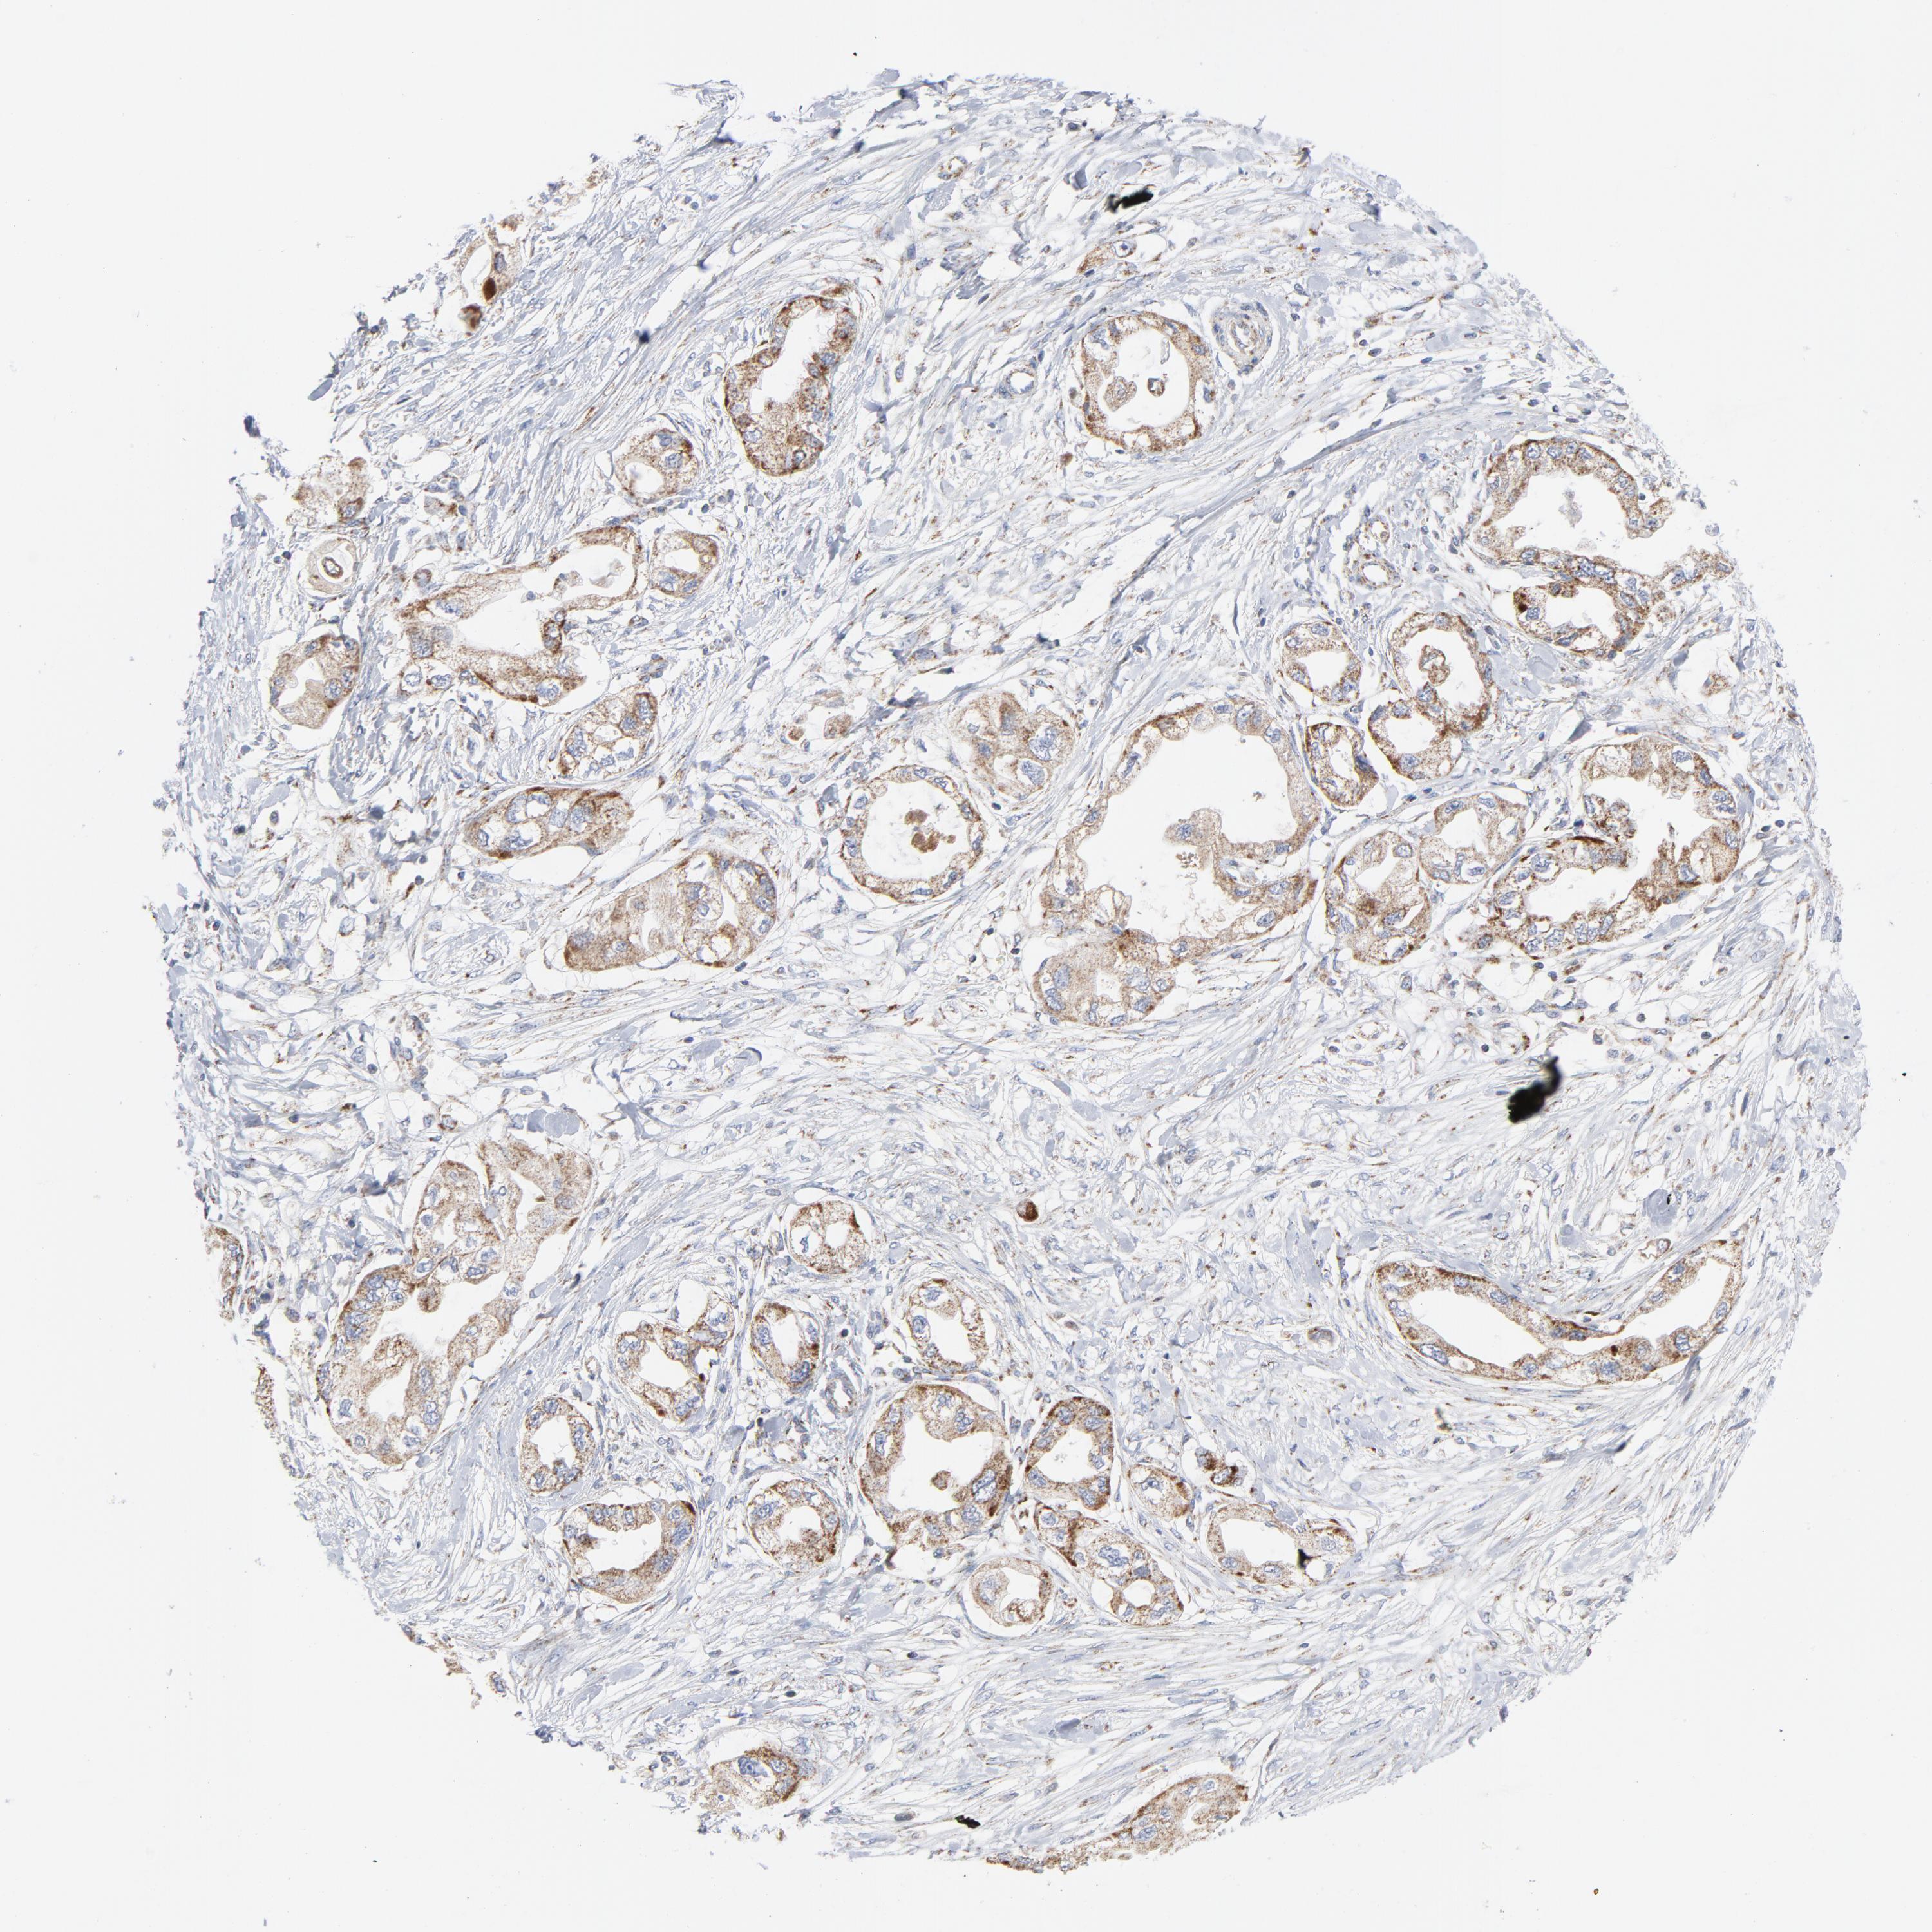

ENDOMETRIAL CANCER - Protein expressioni

A mouse-over function shows sample information and annotation data. Click on an image to view it in a full screen mode. Samples can be filtered based on level of antibody staining by selecting one or several of the following categories: high, medium, low and not detected. The assay and annotation is described here.

Note that samples used for immunohistochemistry by the Human Protein Atlas do not correspond to samples in the TCGA dataset.

Antibody stainingi

Antibody staining in the annotated cell types in the current human tissue is reported as not detected, low, medium, or high, based on conventional immunohistochemistry profiling in selected tissues. This score is based on the combination of the staining intensity and fraction of stained cells.

Each image is clickable and will lead to virtual microscopy that enables deeper exploration of all samples and also displays staining intensity scores, fraction scores and subcellular localization as well as patient and tissue information for each sample.

Antibody HPA001825

Antibody CAB003857

Staining

High

Medium

Low

Not detected

Intensity

Strong

Moderate

Weak

Negative

Quantity

>75%

75%-25%

<25%

None

Location

Nuclear

Cytoplasmic/membranous

Cytoplasmic/membranous,nuclear

Adenocarcinoma, NOS

Neoplasm, malignant, NOS